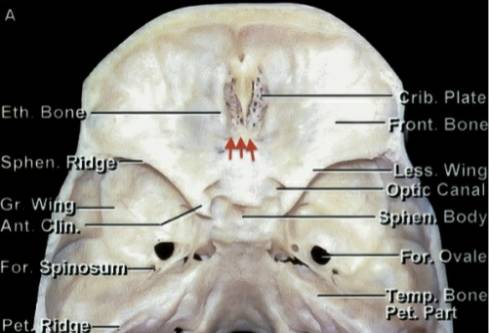

图1. 跨越视神经的(上图)大型的嗅沟脑膜瘤(OGM)最适合开颅手术。如果在冠状位MRI图像上(下图),肿瘤没有明显的超过眼眶的中线(眶中线平面,白色箭头)或者达到视神经外侧,经鼻内镜入路是合适的。

图2. 前、中颅底骨性解剖如上图所示,橘黄色箭头所指的前颅窝筛板及其后方就是典型的嗅沟脑膜瘤(OGM)的起源(图片来自AL Rhoton,Jr)。2:前、中颅底骨性解剖如上图所示,橘黄色箭头所指的是典型的嗅沟脑膜瘤(OGM)的起源(图片来自AL Rhoton,Jr)。